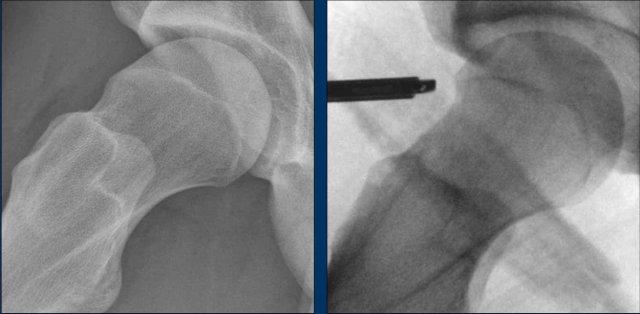

Hình ảnh

Vận động viên thể dục dụng cụ 20 tuổi với các triệu chứng ở hông.

Trên phim chụp AP, vùng đầu-cổ xương đùi trông bình thường.

Trên phim chụp tư thế Dunn, có hình thái Cam ở cả hai bên (mũi tên).